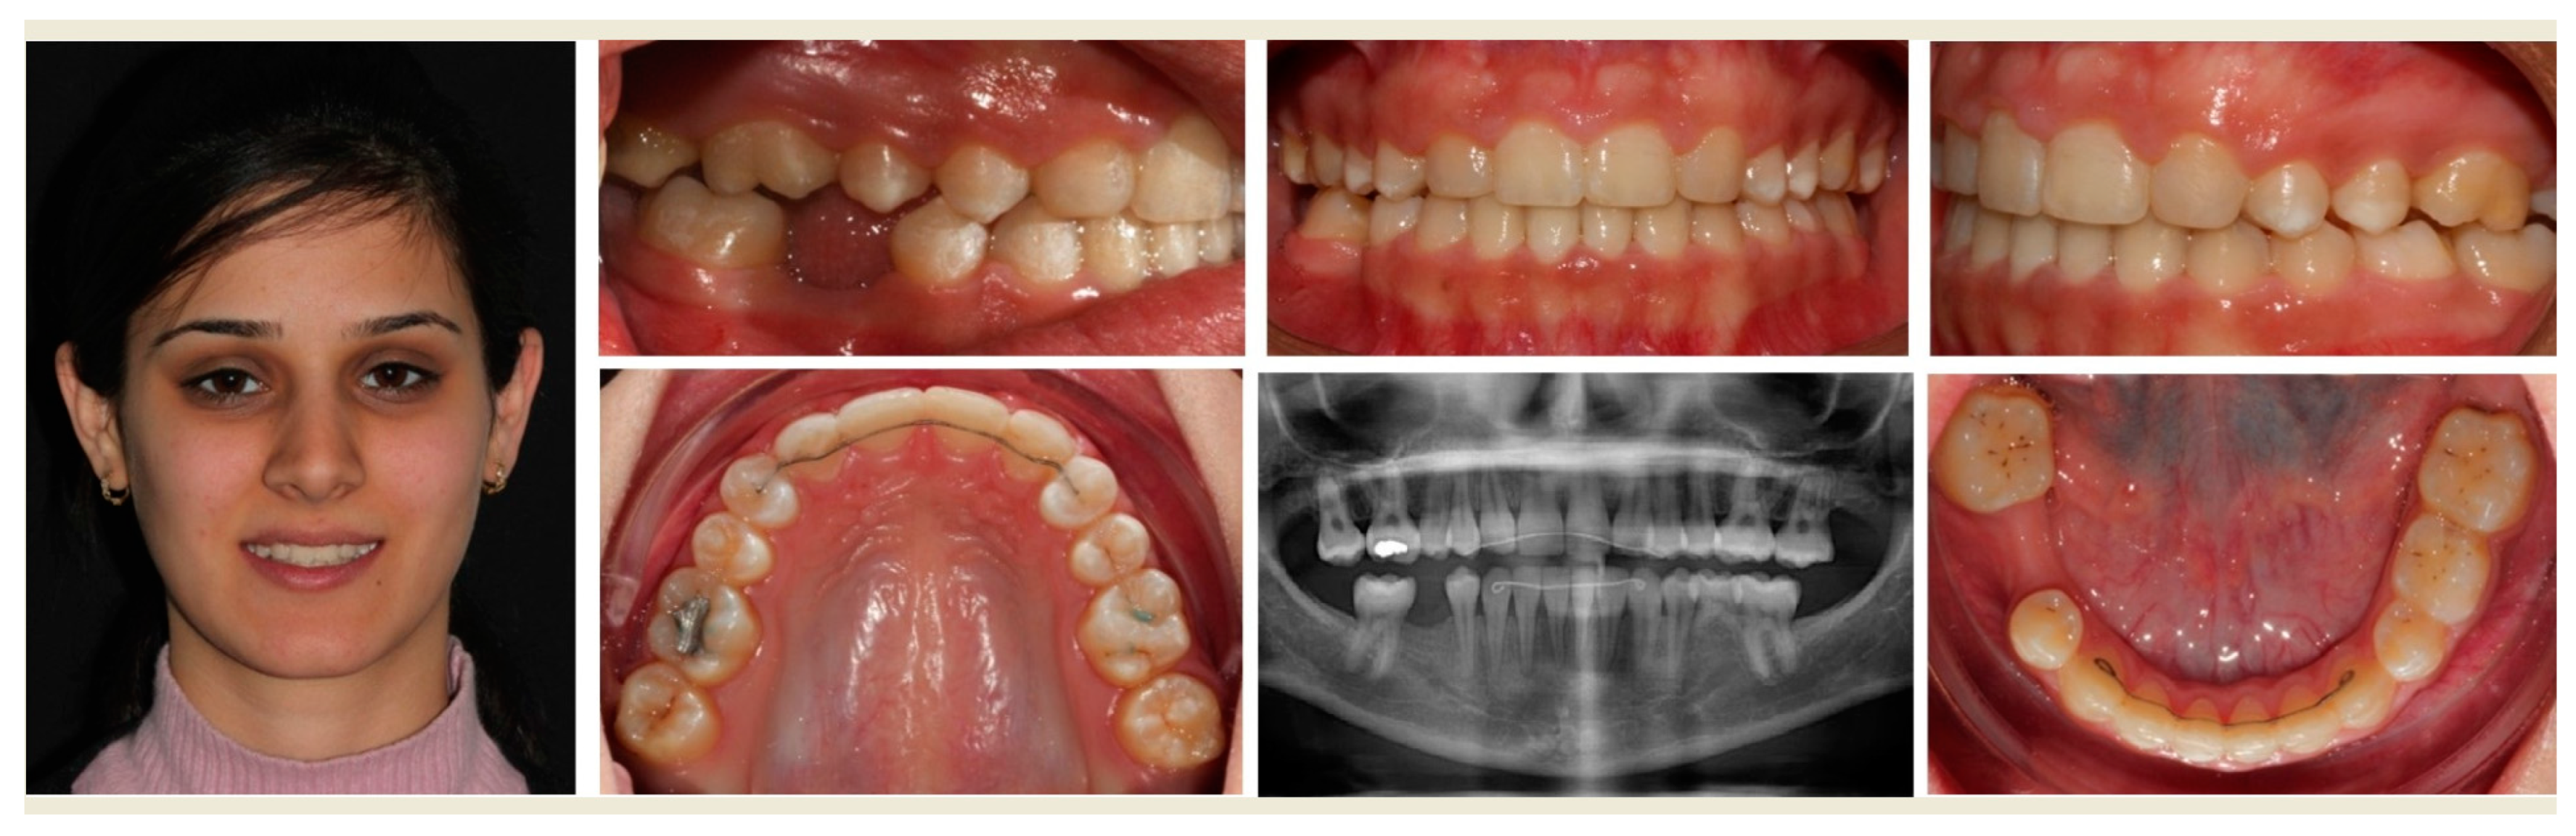

- To demonstrate the clinical management of agenesis of maxillary lateral incisors specifically, because of esthetic concerns, and that of missing second premolars.